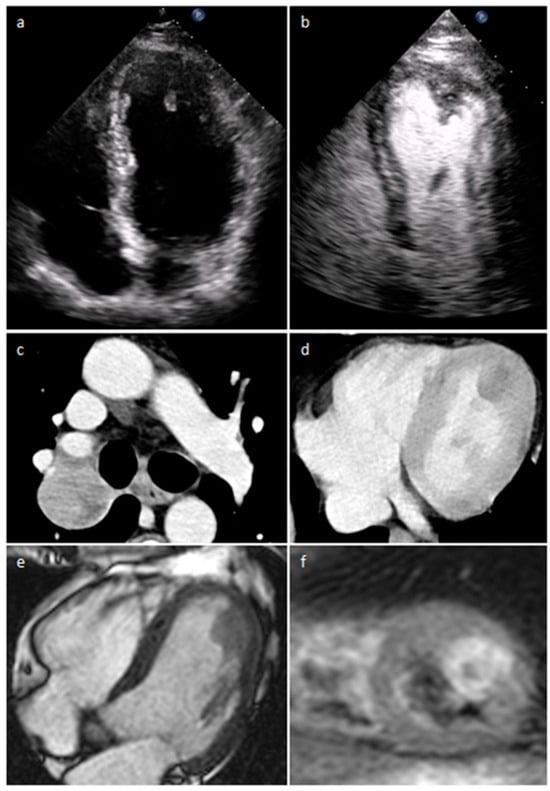

4.1. Myxoma

| Myxoma | Adulthood. Carney complex. | LA | Usually, asymptomatic. Rarely, intracardiac obstruction, embolic events and constitutional symptoms | Mobile mass arising from the IAS | Globular or spherical, with a friable surface and heterogeneous internal echogenicity | Heterogeneous, low attenuation, may be calcified | Isointense T1w, High T2w, heterogeneous LGE |